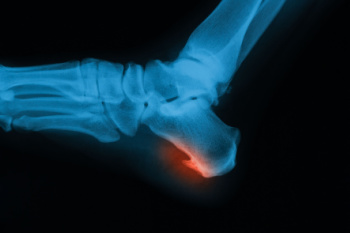

Plantar fasciitis is one of the most common causes of heel pain. The plantar fascia is a ligament that connects your heel to the front of your foot. When this ligament becomes inflamed, plantar fasciitis is the result. If you have plantar fasciitis you will have a stabbing pain that usually occurs with your first steps in the morning. As the day progresses and you walk around more, this pain will start to disappear, but it will return after long periods of standing or sitting.

Plantar fasciitis is a common cause of heel pain that often appears with the first steps in the morning or after periods of rest. The pain is typically sharp and located at the bottom of the heel, sometimes easing as the foot warms up but returning after long activity. It may look normal from the outside, though some patients notice mild swelling or tightness along the arch. Causes include overuse, standing for long periods, improper footwear, tight calf muscles, or changes in activity level. A podiatrist begins with a careful exam and may use imaging to confirm the diagnosis. Treatment includes supportive footwear, custom orthotics, and targeted exercises to stretch and strengthen the plantar fascia. Additional options like anti-inflammatory care or injections may be considered if symptoms persist. If you have plantar fasciitis, it is suggested that you make an appointment with a podiatrist.